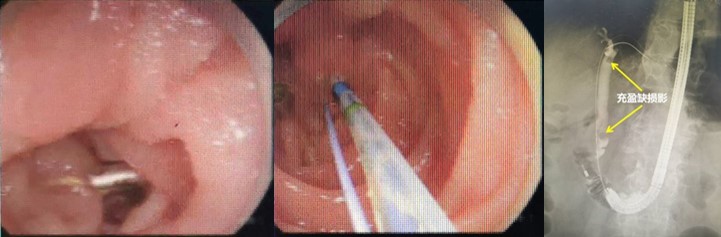

赵刚副主任凭借丰富的经验和精湛的技术,运用胃镜佩戴透明帽顺利找到前期设定的钛夹标记及十二指肠主乳头,然后利用专业器械,在内镜精细操作下,成功进行乳头括约肌切开及球囊扩张术,并最终将胆管内结石顺利取出。整个操作用时不到20分钟。

毕Ⅱ式胃大部切除术后的ERCP操作难度比普通ERCP超出很多,首先就是内镜的选择,按照《中国ERCP指南(2018版)》的建议,推荐首选十二指肠镜进行操作,但十二指肠镜在进镜操作以及寻找输入袢和十二指肠乳头方面明显不如直视镜。消化内科团队通过前期数年来的工作积累,制定了毕Ⅱ式胃大部切除术后ERCP操作的“交大二附院流程”,那就是先进行胃镜检查,由操作者亲自确认术式、输入袢肠管的走行以及十二指肠主乳头的位置,同时在内镜下对乳头进行定位标记,另外,对于输入袢开口较为隐蔽或内镜通过输入袢口较为困难的病例,操作者也会在输入袢口处额外进行标记,以便于后续ERCP操作时的二次寻找。在手术操作过程中,消化内科ERCP团队一般都会选用胃镜佩戴透明帽进行操作,透明帽一方面有利于进镜寻找目标肠袢,另一方面也可提高乳头插管时的镜身稳定性。